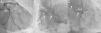

A 74-year-old man, with a history of heavy smoking, presented with unstable angina (Figure 1). Dobutamine stress echocardiography showed ischemia in the right coronary artery territory. Coronary angiography revealed no obstructive epicardial disease in the left dominant circulation (Figure 2A); the right coronary artery (RCA) was a small caliber and tortuous vessel, with only minor atheroma. However, an abnormal vessel arising from the proximal RCA was noted (Figure 2B and C), confirmed as a fistulous connection to the left atrium by multislice computed tomography, which also excluded other vascular anomalies (Figure 3). This was deemed to be causing a coronary steal phenomenon. Exercise myocardial perfusion imaging under anti-ischemic therapy excluded residual ischemia and the patient was successfully conservatively managed (Figure 4).

Multislice computed tomography. (A): 2D multiplanar reformatted image revealing a fistulous connection (arrows) between the proximal right coronary artery (RCA) and the left atrium (LA). (B): 3D volume-rendered image showing the fistula (arrows) arising from the proximal right coronary artery with a retro-aortic course. RA: right atrium; RVOT: right ventricular outflow tract.